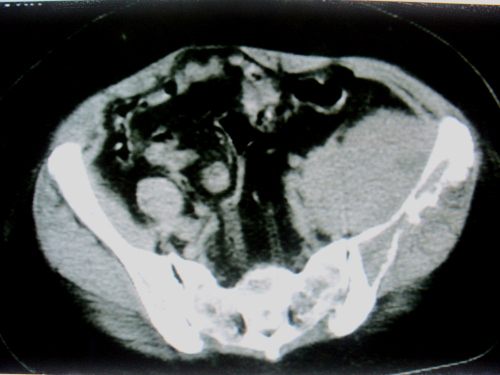

标题: CT18663:女 58岁 左髂区庝痛一年余,加重两月 [打印本页]

标题: CT18663:女 58岁 左髂区庝痛一年余,加重两月

左髂翼内前方软组织样肿块,其密度不均匀,内部呈略低密度的改变,肿块边界清楚,呈宽基底与髂骨“接触”,髂骨骨质破坏。未见明显骨膜反应性增生,及骨旁瘤骨存在。病变不侵犯同侧骶髂关节。

考虑----1 纤维肉瘤-----年龄、表现符合,病变为低度恶性。  或    2  转移瘤-----为髂骨发病率第一病变,需警惕。

左侧髂內肌明显肿大,密度稍不均,可见略低密度的改变,其边界清楚,与髂腰肌间脂肪间隙清晰,与髂骨呈宽基底“接触”,髂骨骨质膨胀性破坏。

考虑左侧髂內肌恶性肿物,建议病检确诊。